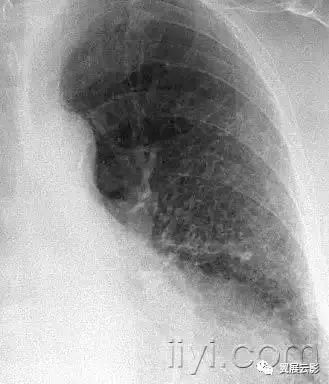

四十一、nodular pattern 粟粒样结节影

本名词尚未明确如何翻译好

平片和CT:粟粒样结节影表现为胸片上无数的小圆形结节,分布弥漫,指教解郁2~10mm内(图)。病变分布广泛但是不一定均匀,在CT上具有三种解剖分布模式:小叶中心性、沿淋巴管或者随机。